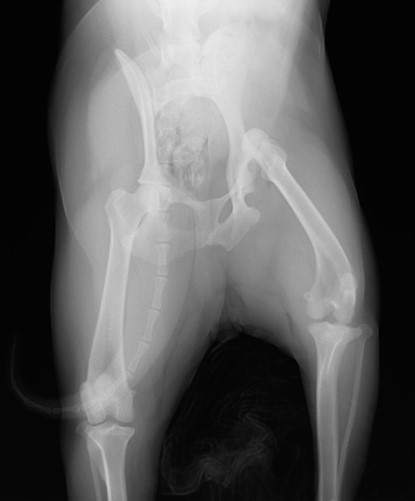

眼球摘出、眼瞼腫瘤切除、チェリーアイ整復、眼瞼縫合、瞬膜フラップ、眼球突出整復、耳介切除、垂直耳道切除、総耳道切除、鼻鏡切除、口腔腫瘍切除(上顎骨切除、下顎骨切除を含む)、各種抜歯(猫の全臼歯抜歯含む)舌腫瘍切除、唾液腺嚢胞切除、皮膚腫瘤切除、断脚(前肢、後肢、片側骨盤切除)、断尾、肺葉切除、胸腺腫切除、心膜切除、横隔膜ヘルニア整復、肝臓腫瘍切除、胆嚢摘出、胃切開、胃拡張胃捻転症候群整復、胃腫瘍切除、腸管切開、腸管腫瘍切除、直腸腫瘍切除(粘膜、全層プルスルーなど)、腎臓摘出、SUB設置手術、脾臓摘出、副腎摘出、膀胱切開、膀胱腫瘍切除(部分切除、全摘出、膀胱尿道一括切除など)、卵巣腫瘍切除、精巣腫瘍切除、卵巣子宮全摘出、肛門嚢切除、各種骨折、膝蓋骨脱臼整復、股関節脱臼整復、大腿骨頭切除、椎間板ヘルニア(各種椎弓切除術)、各種リンパ節切除 など